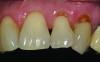

Total removal of the decay was performed. To keep the preparation minimally invasive, a caries indicator (Seek®, Ultradent Products, Inc., www.ultradent.com) was used so that only the infected dentin was removed. Minimally invasive burs (Micro Prep Kit, Komet USA, www.kometusa.com) were used, which are helpful when minimal tooth removal is an objective (Figure 3). A long-bevel margin (889M-007, Komet USA) was then created along the facial side so that the final composite resin could be blended to the existing dentition. A thin layer of resin-modified glass ionomer (RMGI) (GC Fuji II™ LC, GC America Inc.) was sculpted and light-cured to cover the affected dentin.

Before bonding, the enamel was etched with 37% phosphoric acid (ETCH-37™ 37% Phosphoric Acid Etchant, BISCO, Inc., www.bisco.com). A dentinal adhesive (ALL-BOND UNIVERSAL®, BISCO, Inc.) was placed, blown thin for 10 seconds with forceful compressed air, and then light-cured for 20 seconds (Figure 4). Using an injectable composite resin (G-ænial Universal Flo), a sequence of composite resin layering was performed to blend the composite resin to the existing tooth and create a natural polychromatic effect. To match the chromaticity along the gingival area, an opacious dentin shade, AO2, was bonded over the RMGI to mimic the lost dentin (Figure 5). Using a free-hand sculpt technique, universal shade A2 was injected over the opacious dentin composite resin with an emphasis on placing a convex anatomy to simulate natural dentition. Because of the chameleon effect and the depth of color of the body shade A2, no other shades were needed (Figure 6).

After final light-curing, esthetic contours were refined using aluminum oxide finishing discs (Sof-Lex™ Finishing Disc, 3M ESPE, www.3mespe.com) and Q-Finisher® composite resin finishing burs (H50AQ, Komet USA). Finally, microdiamond-infused polishing wheels and 1.0-µm microdiamond polishing paste brought out the surface luster of this injectable composite resin (Figure 7 and Figure 8). Using proper technique and state-of-the-art dental materials, natural color, contour, and finish to mimic tooth were achieved.12